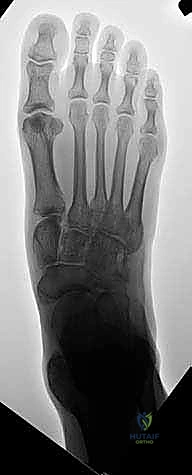

IMAGING AND OTHER DIAGNOSTIC STUDIES

Radiographs reveal the static anatomic relationships between bones. They should not be used, in and of themselves, as an indication for treatment.Radiographs of the flatfoot are not necessary for diagnosis. They may be indicated for the assessment of pain or decreased flexibility and for surgical planning.Weight-bearing anteroposterior (AP), lateral, medial oblique, and axial (or Harris) views are appropriate for those indications ( FIG 4).The lateral oblique (nonstandard) view is helpful for the identification of an accessory navicular that could be the cause of a painful medial prominence in the midfoot that is not the head of the talus.An AP ankle radiograph is useful to determine whether any of the hindfoot valgus deformity is in the tibiotalar joint.A computed tomography (CT) scan in all three planes and with three-dimensional (3-D) reconstruction is the imaging modality of choice for assessment of a rigid flatfoot, particularly when there is a high degree of suspicion for a subtalar tarsal coalition. The published criteria for operative management of a subtalar tarsal coalition are based on CT scan findings.A bone scan can help with the assessment of atypical pain in a flatfoot.A magnetic resonance imaging (MRI) may be indicated if these other imaging studies fail to reveal the etiology for atypical pain in a flatfoot. An MRI scan is not the imaging study of choice for evaluation of a tarsal coalition. ## DIFFERENTIAL DIAGNOSIS Flexible (hypermobile) flatfootFlexible (hypermobile) flatfoot with short Achilles tendon Rigid flatfootCongenital oblique talus Congenital vertical talus SkewfootPauciarticular juvenile rheumatoid arthritis affecting the subtalar joint Peroneal spastic flatfoot ### FIG 4 • Standing radiographs of a flatfoot. A. AP image demonstrates the external rotation component of eversion or valgus of the subtalar joint. B. The lateral image reveals plantarflexion of the talus, sag at the talonavicular joint, and a low calcaneal pitch. (From the private collection of Vincent Mosca, MD.)

theoretically, protect the ankle and midtarsal joints from early degenerative arthrosis by avoiding arthrodesis. ### FIG 5 • Final radiographs in the bivalved cast. A. On the AP view, note the correction of the external rotation deformity at the talonavicular joint as also assessed by the talo-first metatarsal angle. B. The lateral view demonstrates dorsiflexion of the talus, alignment at the talonavicular joint, correction of the talo-first metatarsal angle, and normalization of the calcaneal pitch. (From Mosca VS. Calcaneal lengthening osteotomy for valgus deformity of the hindfoot. In: Tolo V, Skaggs D, eds. Master Techniques in Orthopaedic Surgery: Pediatric Orthopaedics. Philadelphia: Lippincott Williams & Wilkins, 2008:263-276.)